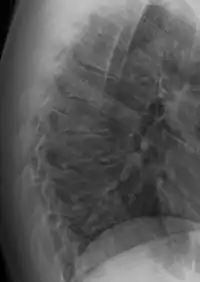

In addition to the pain associated with Scheuermann's disease, many sufferers of the disorder have loss of vertebral height, and depending on where the apex of the curve is, may have a visual 'hunchback' or 'roundback'. It has been reported that curves in the lower thoracic region cause more pain, whereas curves in the upper region present a more visual deformity. Nevertheless, it is typically pain or cosmetic reasons that prompt sufferers to seek help for their condition. In studies, kyphosis is better characterized for the thoracic spine than for the lumbar spine.[6][7]

The seventh and tenth thoracic vertebrae are most commonly affected. It causes backache and spinal curvature. In very serious cases it may cause internal problems and spinal cord damage, but these cases are extremely rare. The curvature of the back decreases height, thus putting pressure on internal organs, wearing them out more quickly than the natural aging process; surgical procedures are almost always recommended in this case.

Diagnosis is typically by medical imaging. The degree of kyphosis can be measured by Cobb's angle and sagittal balance.